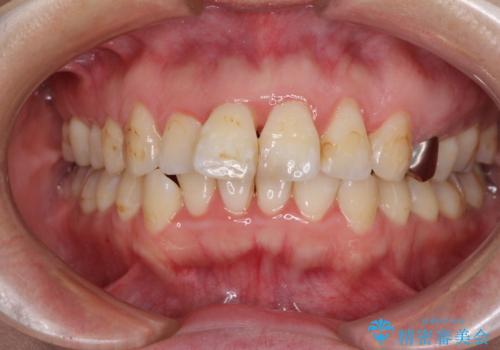

- 出っ歯と口の閉じにくさ、デコボコを気にして来院された患者様です。

口元の突出感を改善するため、上下左右第一小臼歯4本の抜歯を行い、ワイヤー装置による矯正治療を行うこととしました。